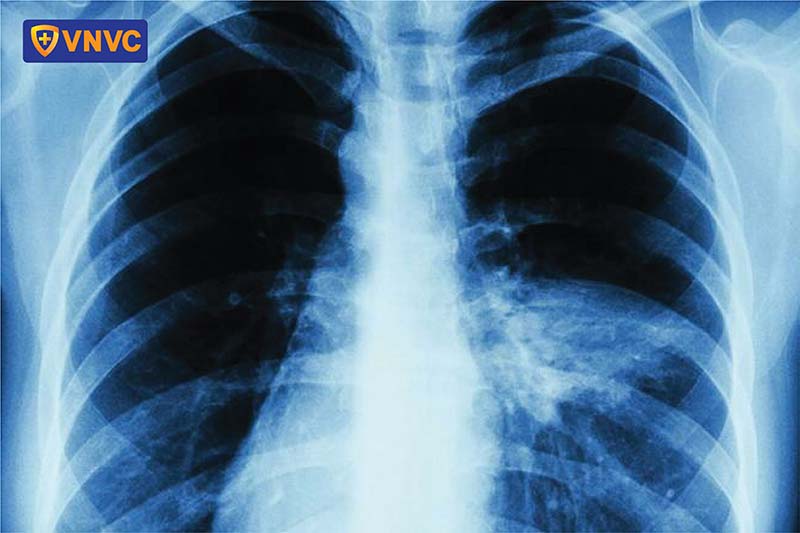

- Viêm phổi: Biến chứng này thường xuất hiện ở người lớn vào ngày thứ 3 đến thứ 5 của bệnh, dẫn đến suy hô hấp, phù phổi và gây nguy hiểm đến tính mạng.